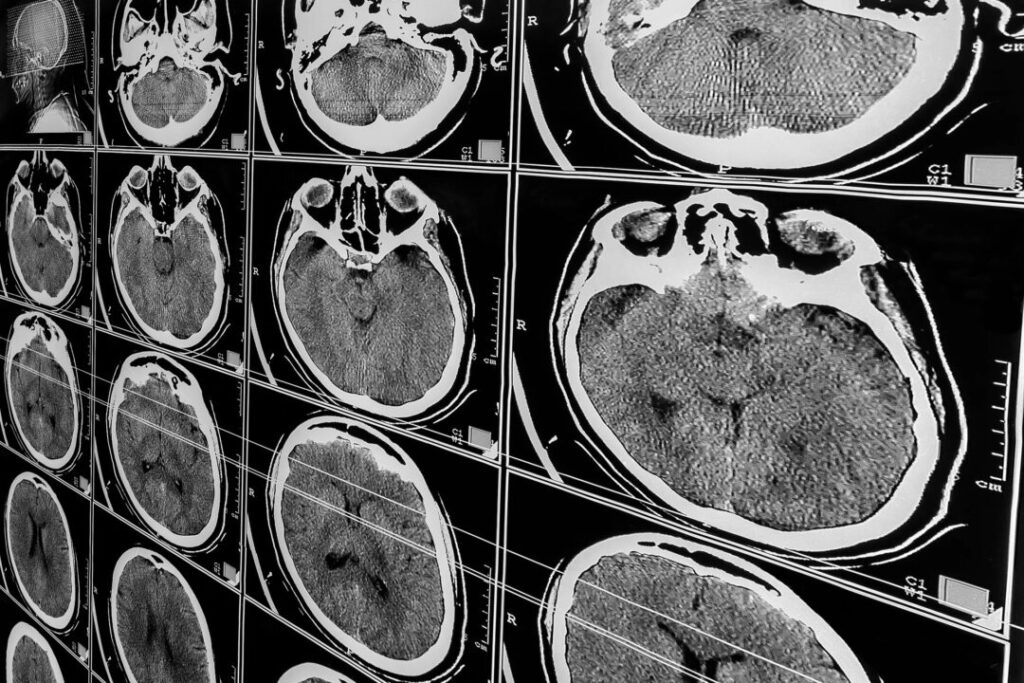

反応なしでも意識あり? 脳損傷患者の新たな可能性

意識と患者ケアに対する私たちの理解を変える可能性のある発見により、脳損傷後に反応がないと判断された患者の4人に1人が、実際には周囲を認識している可能性があることが研究者の調査で明らかになりました。

8月に『New England Journal of Medicine』誌に掲載されたこの研究は、「認知と運動の解離(CMD)」として知られる状態に光を当てました。この研究は、コロンビア大学アーヴィング医療センターやワイルコーネルメディスンを含む複数の医療センターで、241人の反応のない患者を対象に行われました。この研究は、重度の脳損傷患者の意識に関する私たちの理解に疑問を投げかけています。

この現象は、患者が命令に対して外見上何の反応も示さないにもかかわらず、「脳波検査(EEG)や機能的磁気共鳴画像法(fMRI)を行っている際に、被験者が意識を持っていることを示す脳の活動パターンが確認される場合」があります。